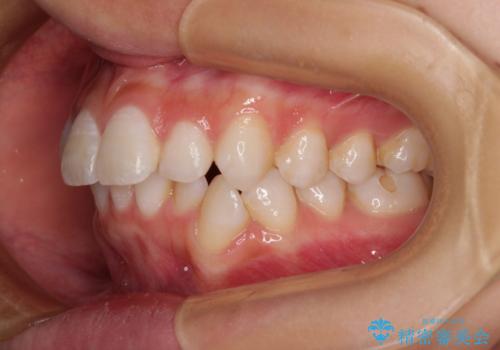

斜め前に飛び出した前歯 抜歯矯正で素敵な横顔に

下唇に前歯が当たって跡が残ってしまう状態でしたが、スッキリとした口元に仕上げることができました。

- 口を閉じたときに飛び出してしまう上顎前歯を気にして来院された患者様です。

下顎はデコボコが気になっていたため、上下左右第一小臼歯4本を抜去して、ワイヤー装置にて口元の突出感を改善するよう矯正治療を行うこととしました。